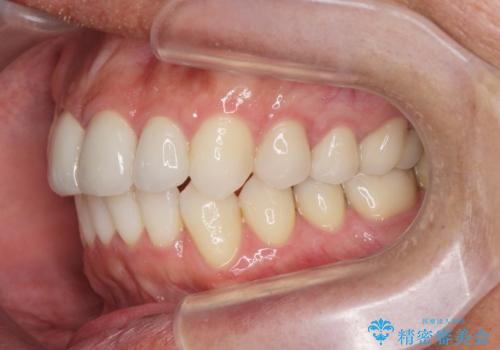

矯正と虫歯のセラミック治療 総合歯科治療の実践

- 突き出た前歯の角度の改善と虫歯治療の改善を求めて来院されました。

虫歯を除去したのち、マウスピース矯正治療を行い、歯並びやがたつきを改善したのち、セラミックに置き換えることで審美性の向上を計画します。

矯正や虫歯治療、セラミック治療といった複合的な治療を一医院で行うことができるのが当法人の大きな特長です。